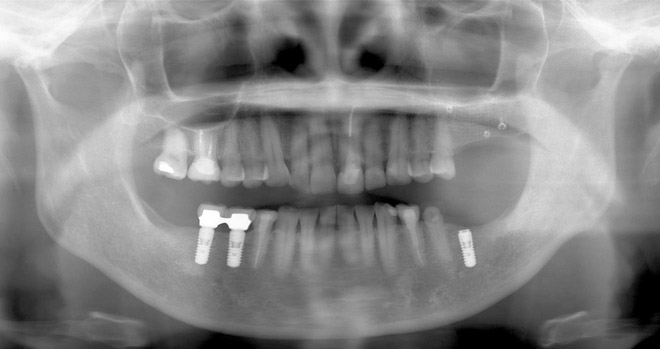

OPG (オルソパントモグラフ)

スクリーニング(初期全体評価)の為の低被曝なX線検査。

顎骨、歯、歯周組織、顎関節、解剖学的リスク等の概略を評価可能。

※この段階でのCT撮影は過剰診査となりますので注意。